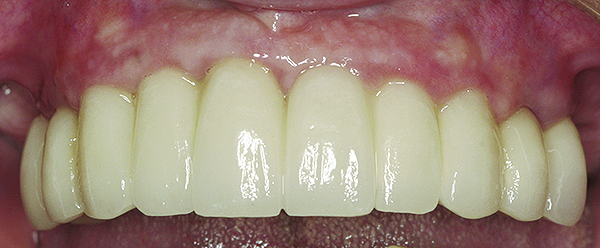

Accordingly, if an increased rate of bone loss was selected to represent the pace of osseous resorption under dentures, a comparison between the rates of bone loss under dentures and around implants would indicate that implants preserve bone. Furthermore, the preponderance of data document that usually the amount of bone reduction per year around implants, in the absence of peri-implantitis, is so small that it has a negligible effect on the survival of implants, and it would take years to manifest noticeable bone loss and recession. For example, in areas under implant-supported prostheses (Figure 15), the ridge does not routinely manifest bone resorption and recession.66,67 However, there are patients who demonstrate different degrees of bone loss, and the reason for this is unknown.

Fig 15. Clinical view of a 65-year-old female patient 5 years after insertion of a porcelain-fused-to-metal prosthesis on six threaded titanium implants in the maxilla (site Nos. 5, 7, 8, 10, 12, and 13). There is no clinically observable recession around the prosthesis or implants.

Figure 15